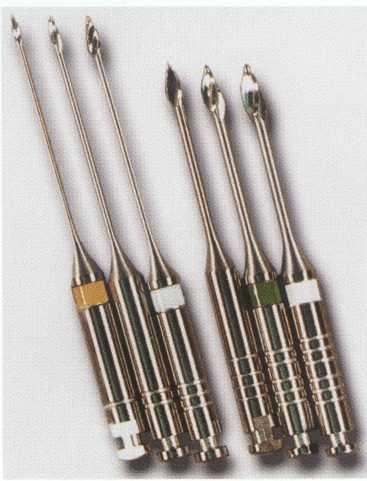

FIGURE 2-7 The Analytic ultrasonic gold nitride tips are available in sizes #2 through #5, and NiTi tips are available in sizes #6 through #8. Pictured left to right are #2, #3, #6, #7, and #8. Many other configurations are available.

Ultrasonics

The CPR tips are available in nitride (gold-yellow) and NiTi (green, blue, and purple) (Figure 2-7). The extremely fine tips coupled with the small handpiece allow unprecedented visibility (Figure 2-8). Ultrasonic tips can be used to remove pulp stones and to cut dentin while locating additional canals.